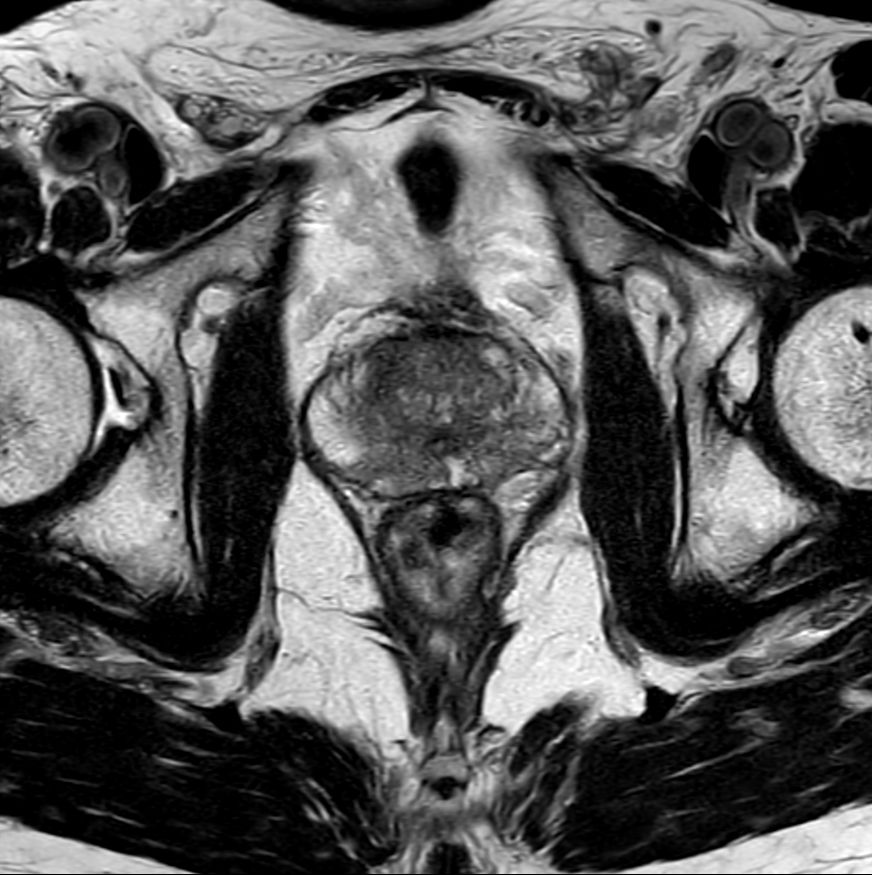

For prostate exams, the MSK M coil can be used in combination with the posterior coil, delivering exceptional quality MR images and high patient satisfaction.

Premium signal-to-noise ratio is achieved via dStream, providing outstanding image resolution.